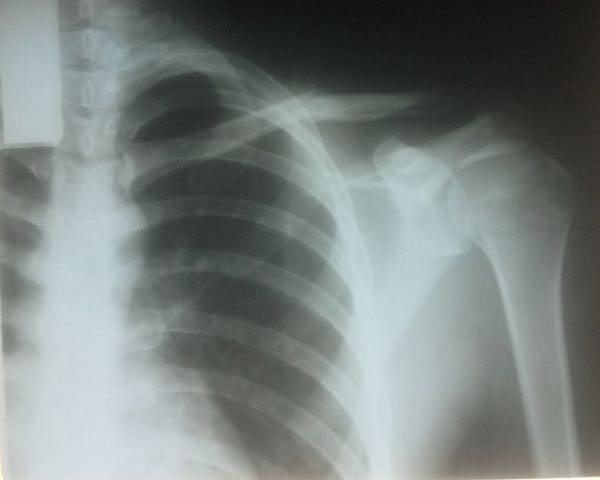

Se fractura la clávicula Issac Fonseca y queda fuera del cartel final de triunfadores